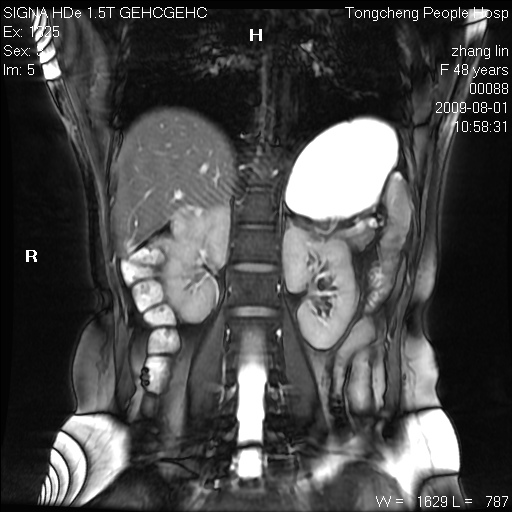

女,48岁。健康体检,彩超发现右肾占位性病变。平素健康。

临床诊断:右肾占位性病变,性质待定(囊肿?肿瘤?)。

上中腹部mr平扫+增强扫描,图像如下:

右肾上极见一类圆形病灶,t1wi呈等信号t2wi呈等高混杂信号,三期增强无强化,边界清---考虑囊肿出血。

肝囊肿